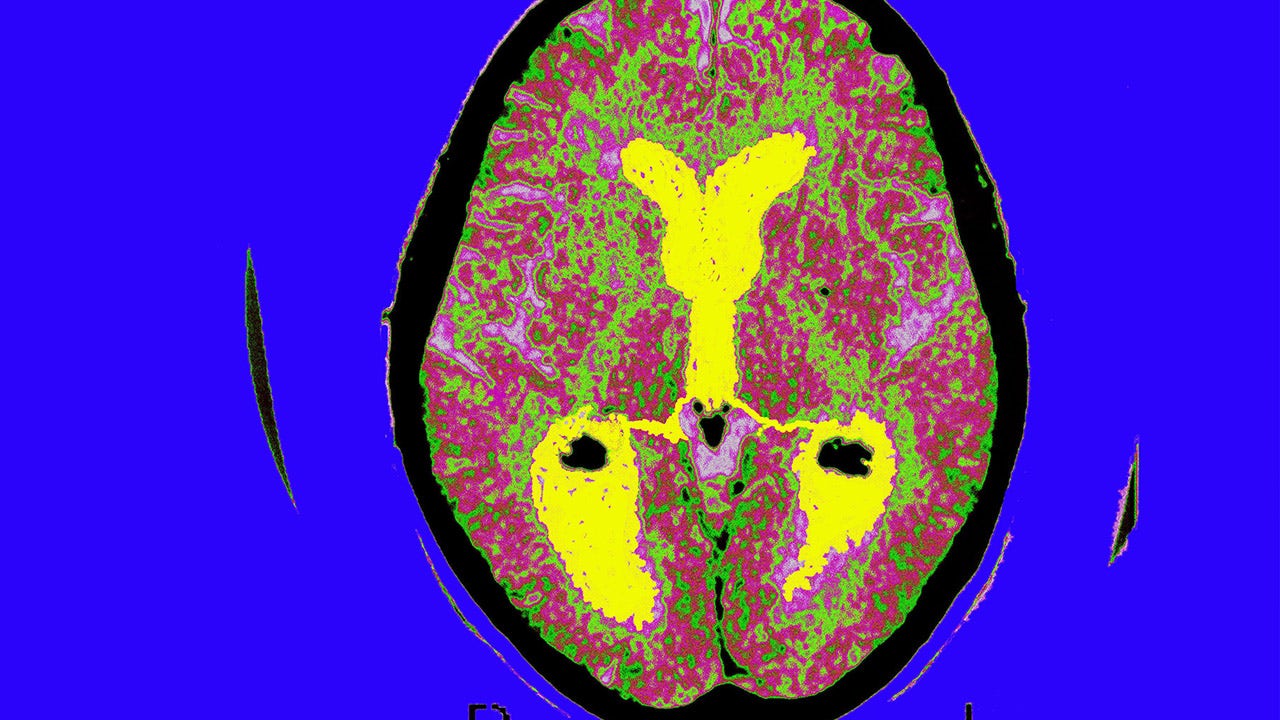

Instead, the agency took another approach and gave the drug conditional approval based on a promising sign: its success in getting rid of a buildup of sticky plaque in the brain that is thought to play a role in Alzheimer's disease.

Under its so-called accelerated approval program, the FDA is requiring Biogen to conduct a new study definitively answering whether Aduhelm's effect on plaque truly slows mental decline in patients. Other Alzheimer's drugs on the market only temporarily ease symptoms.